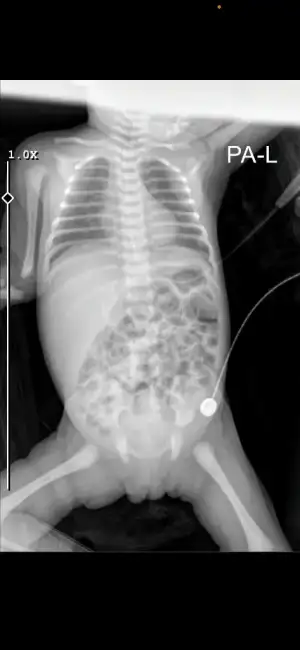

Günaydın bugünkü röntgeni bu. Bakabilir misiniz

Eklentiler

• IMG_2215.webp

IMG_2215.webp

12,8 KB · Görüntüleme: 64